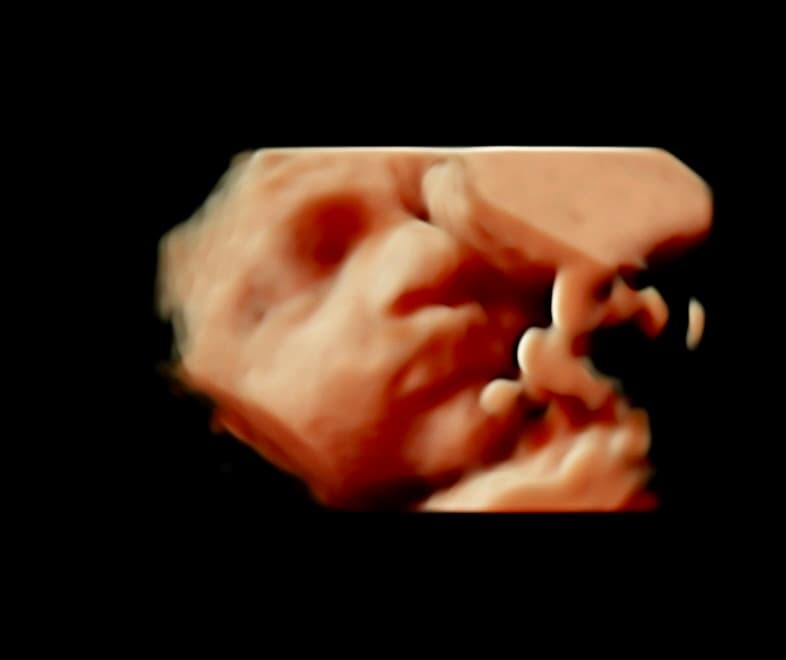

At Magnolia Fetal Imaging, we provide a warm, relaxing environment where you can bond with your baby through advanced 3D/4D & HD ultrasound technology. Our studio focuses on capturing precious keepsake moments for families — gender reveals, early looks, and high‑definition images you will cherish for a lifetime.

All sessions are non‑diagnostic and designed purely for bonding and keepsake entertainment.